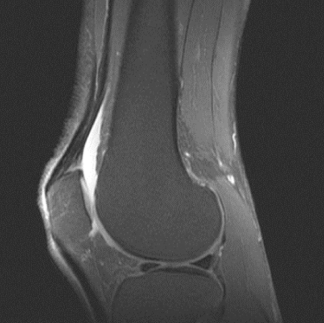

영상검사: 엑스레이, 초음파, MRI 등으로 관절 상태 확인